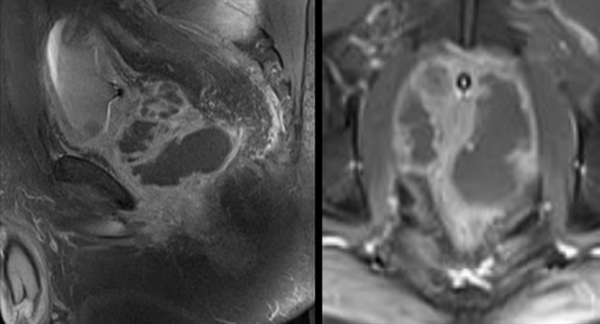

Пациент С., 1945 года рождения, считает себя больным с 2012 г., когда впервые отметил затруднения при мочеиспускании, однако к врачам не обращался. В июле 2016 г. при плановом обследовании по месту жительства выявлено повышение ПСА до 276 нг/мл, выполнена трансректальная биопсия предстательной железы под ультразвуковым контролем. Больной для дальнейшего обследования и лечения обратился в поликлинику МНИОИ им. П.А. Герцена. При гистологическом исследовании, пересмотре стекол и блоков гистологических препаратов в МНИОИ им. П.А. Герцена выявлен инфильтративный рост ацинарной аденокарциномы 7 (4+3) баллов по Глисону, занимающей до 80% площади биоптатов. Пациент самостоятельно выполнил ПЭТ/КТ с холином. По данным ПЭТ/КТ, в обеих долях простаты определяются очаги накопления радиофармпрепарата (РФП) неоднородного характера, с наиболее выраженным накоплением РФП до макс. SUV 12,09 в периферической зоне слева и переходных зонах предстательной железы с обеих сторон (рис. 1), Рис. 1. Компьютерная томограмма малого таза (а). Накопление РФП в предстательной железе (б). в семенных пузырьках слева и справа, а также в наружном подвздошном лимфатическом узле слева макс. SUV 4,47, размером 1,3×0,7 см.

Пациент К., 1965 года рождения, при плановом обследовании в поликлинике по месту жительства в марте 2017 г. выявлено повышение уровня ПСА до 6,5 нг/мл, в связи с чем в ГКБ № 29 Москвы выполнена трансректальная биопсия предстательной железы, гистологически верифицирована ацинарная аденокарцинома 6 (3+3) баллов по Глисону. Больной самостоятельно обратился в МНИОИ им. П.А. Герцена. При пересмотре стекол препаратов биопсии предстательной железы в условиях патоморфологического отделения МНИОИ им. П.А. Герцена на фоне гиперплазии предстательной железы с очагами атрофии в 5 фрагментах из 12 выявлен рост ацинарной аденокарциномы 7 (4+3) баллов по Глисону, занимающей до 100% площади столбиков. По данным УЗИ и МРТ малого таза, предстательная железа размером 42×34×30 мм, объемом до 30 см 3 (рис. 3). Рис. 3. Магнитно-резонансная томограмма малого таза.